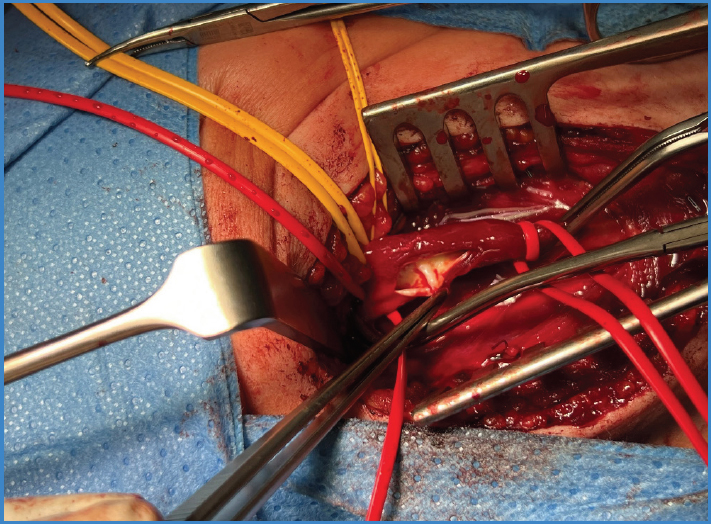

Mujer de 37 años sin antecedentes médico-quirúrgicos reseñables. Acude a urgencias por hemiplejia izquierda de 3 horas de evolución. Se diagnostica mediante tomografía computarizada (TC) cerebral de infarto de arteria cerebral media derecha, por lo que se realiza trombectomía mecánica urgente. Durante el procedimiento, se observa en la arteriografía septo no oclusivo en el segmento bulbar de la arteria carótida derecha, sugestivo de carotid web (Fig. 1). Descartado el origen cardíaco y como presentaba ritmo sinusal y ecocardiograma sin alteraciones, se solicita angiografía por TC, que confirmó dicho diagnóstico. Se decide endarterectomía de carótida interna derecha (Fig. 2) y cierre con parche de vena safena interna autóloga. Fue dada de alta después de 72 horas sin complicaciones. Posteriormente se observa permeabilidad a los 6 meses y ausencia de reestenosis.